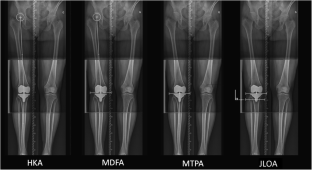

Preoperative and postoperative measurements were taken for 55 consecutive kinematically aligned TKAs, including the joint line orientation angle (JLOA), formed between the joint line and a line parallel to the floor.

The mean medial proximal tibial angle (MPTA) was 3.4° varus pre-operatively (1.7° valgus to 7.9° varus, SD 2.0), and 3.0° varus postoperatively (5.5° valgus to 6.5° varus, SD 2.1). The mean postoperative JLOA was 1.0° varus with a smaller range than the MPTA (2.6° valgus to 6° varus, SD 1.9). The difference between these two measurements was significant (mean 2°, SD 2.5, p < 0.001).

Relative to the mechanical axis, 33 tibial components would be considered at risk outliers, being orientated at more than 3° in varus or valgus. However, only six components were outside this range relative to the vertical, all in varus (mean 4.2°). This latter measurement may better represent how the prosthesis is functionally loaded and is similar to mechanically aligned TKAs with good survivorship. This may help explain why kinematic alignment does not lead to higher earlier failure rates that may result if similar orientations were seen with mechanically aligned TKA.